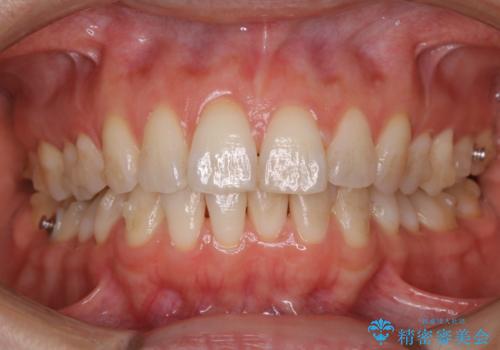

歯科医院にて染め出しをして歯磨き指導と専門的なクリーニング(PMTC)

- 久しぶりの来院のためクリーニング希望とのことでした。染め出しを行い、歯ブラシ指導とPMTC30分コースを行いました。